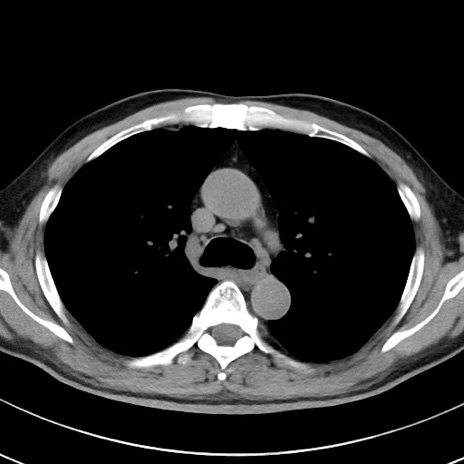

【腹部TIPS】症例29 参考症例 CT(横断像)

症例

70歳代男性